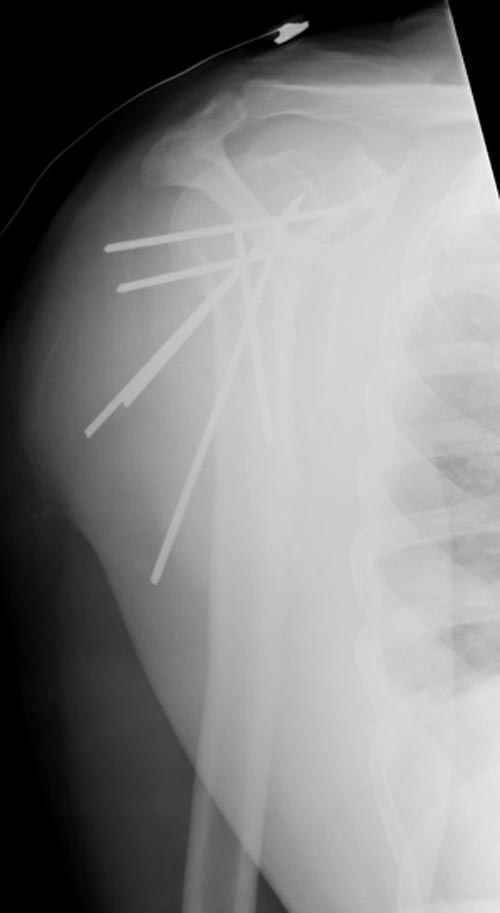

Здесь случай перелома-вывиха плеча, больному 56 лет, после "дважды" закрытой неудачной репозиции, опять же ургентно взяли в операционную, после полного общего обезболивания попытались сделать репозицию, и фиксацию провели спицами.

Больной находился в повязке, примерно напоминяющей косыночную, рекомендованы движения в локтевом суставе и маятниковые движения в плече, спицы удалены в три недели (были случаи миграции)

Больной амбулаторный, предупрежден на случай осложнения АВН головки.